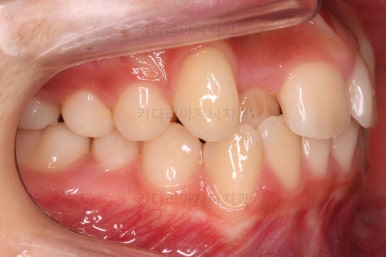

연산동치과 초진 시, 입안의 모습입니다.

보시다시피 앞니쪽이 많이 삐뚤고요. 어금니쪽이 긴밀하지 못한 부정교합이 있네요.